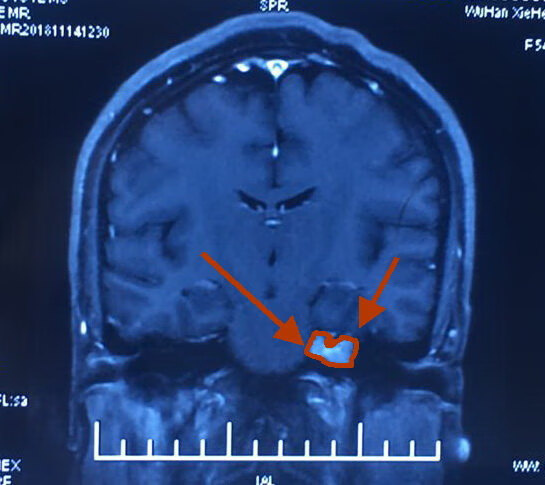

她,45岁,左耳失聪三年。经过核磁共振检查发现左侧桥脑小脑角区占位性病变,考虑听神经瘤。

肿瘤大小1.8cm。

术前影像如下:

采用两端相向汇聚法-显微外科技术切除左侧听神经瘤。

高速磨钻磨开内听道骨性后壁显露面神经内听道端,面神经出脑干端分别显露确认,再瘤内切除减压,两端相向分离肿瘤面神经界面,最后全切肿瘤;术中电生理监测面神经和脑干功能。面神经损伤极小。